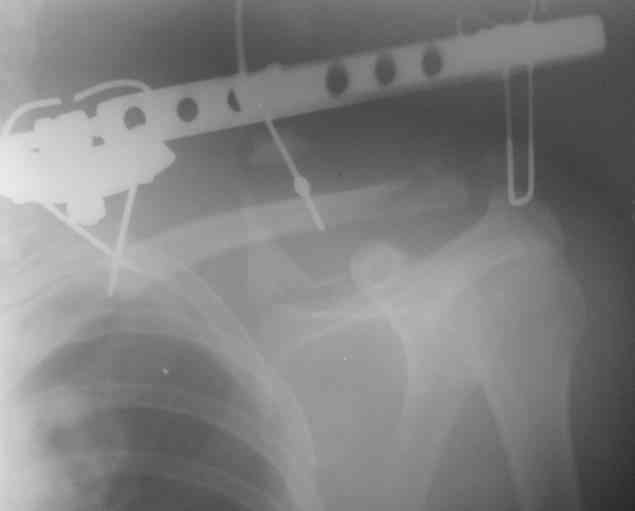

DK> На какой срок решили оставит в аппарате, и что за аппарат?

Планирую через четыре недели сделать рентген-контроль с решением вопроса об удалении АВФ. Аппарат смонтирован из деталей аппарата Илизарова. Картинки в приложении.

К сожалению оригинального аппарата Сушко нет в наличии (даже в глаза не видел), но использовался сам принцип метода по Сушко-Илизарову. Цитирую из "Основ по чрезкостному остеосинтезу аппаратом Г.И. Илизарова" (Л.Н.Соломин, 2005): 1. В каждый костный фрагмент должно быть введено не менее двух 2-мм консольных спиц, расположенных под углом к друг другу. 2. Места введения спиц должны располагаться вблизи суставных концов ключицы.

3. Точки введения спиц должны находиться на верхней поверхности ключицы.

4. Плоскость расположения спиц должна совпадать с продольной осью костных фрагментов.

5. При диафизарных переломах спицы проводят через оба кортикальных слоя.

6. При переломо-вывихах акромиального конца ключицы консольные спицы в акромиальный конец ключицы вводят только до упора в противолежащий

кортикальный слой; в акромиальный отросток лопатки консольные спицы не вводят, а используют спицу Киршнера "acr.,6-12", концы которой П-образно загибают навстречу друг другу.

7. Расстояние между поверхностью кожи и внешними опорами должно быть минимальным - в пределах 1,5-2 см.